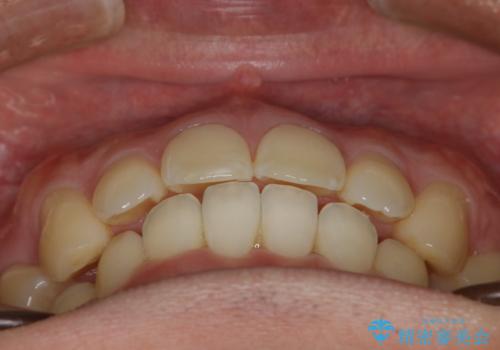

がたつき、口ゴボ(出っ歯)、真ん中のずれを抜歯矯正治療で治す。ワイヤー矯正治療

- 口元の突出感とがたつきを気にして来院されました。

もともとの歯の根っこの位置の関係で、治療途中において上下の真ん中の位置がずれてしまいました。機能的には問題ありませんが患者様と相談し、期間を延ばした上で真ん中を合わせる治療を追加で行いました。